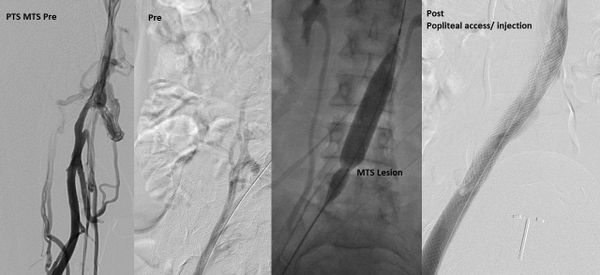

استشاري جراحة الأوعية الدموية و القسطرة التداخلية الطرفية